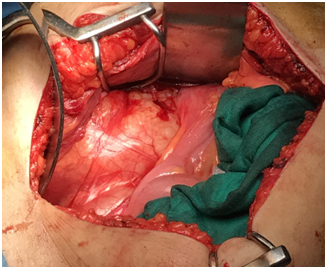

We present here the case of a 50-year-old woman who consulted for a mild right low back pain with palpable abdominal mass since several months. The clinical examination revealed a painless tumefaction of the right iliac fossa (Figure 1). A CT-scan performed showed a large right retroperitoneal cystic polylobed mass, well limited, measuring 15 cm x 10 cm x 9 cm, pushing forward the digestive loops and pushing up the right kidney, containing calcifications, without enhancement after contrast injection, and without evidence of adjacent structures infiltration, evoking a retroperitoneal cystic lymphangioma (Figure 2) and (Figure 3). The patient underwent an exploratory laparotomy, which showed a large whitish retroperitoneal cyst, extending from the right iliac fossa to the right hypochondrium (Figure 4). Given the appendix was not individualized, we suspected then, during surgery, an appendiceal mucocele. During dissection, we assisted to a tumoral rupture, and approximately 500 milliliters of a thick, gelatinous mucoid substance was sucked. The peritoneal cavity was already protected by surgical drape. We went an en-bloc and complete resection of the tumor (Figure 5). The post-operative course were normal. The histological study concluded to a mucinous cystadenoma (Figure 6). After a one-year follow-up, control CT-scans showed no signs of recurrence.

The World Health Organization (WHO) classifies appendiceal mucoceles among retentive cyst (18 %), diffuse or localized mucosal hyperplasia (20 %), mucinous cystadenoma (52 %) and mucinous cystadenocarcinoma (10 %).3 The therapeutic strategy is based on the total resection of the tumor, and avoiding any rupture that would lead to iterative surgical procedures.11,13,21–24 Hyperthermic Intraperitoneal Chemotherapy (HIPEC) followed by postoperative chemotherapy may also be necessary, especially in cases of recurrences and pseudomyxoma peritonei.25 A open-surgery approach is often preferred to laparoscopical approach, given the high risk of dissemination, even if a retrieval bag is used.26,27,28 The outcome of retentives cysts and mucinous cystadenoma is far way better than mucinous cystadenocarcinoma, with a 100 % versus 30 % overall survival.6,9,24,29 There is no surveillance recommendations, but it is rightful to request a CT-scan every 6 months.